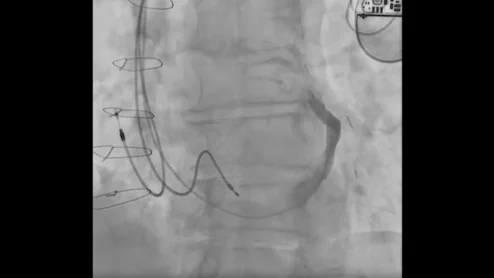

Interventional cardiologists in Canada have performed the world’s first implant of a new coronary sinus reducer designed to treat chest pain patients who see no benefits from other available interventional or surgical treatments. The A-Flux Reducer System was designed and developed by VahatiCor, a new medical device company associated with California-based T45 Labs.

The A-Flux Reducer System by VahatiCor was designed to “conform seamlessly” to any patient’s anatomy, and it can be repositioned or retrieved as necessary.

V-Wave has gained considerable attention or its Ventura Interatrial Shunt System, a small implantable device designed to reduce pressure on the left atrium and the lungs in patients with heart failure with reduced ejection fraction (HFrEF). The Ventura device includes a nitinol hourglass-shaped frame that anchors to the patient’s fossa ovalis in a way that prevents migration or embolization. It is implanted via an interventional procedure with fluoroscopy and echocardiography guidance.

V-Wave has gained considerable attention for its Ventura Interatrial Shunt System, a small implantable device designed to reduce pressure on the left atrium and lungs of HFrEF patients.